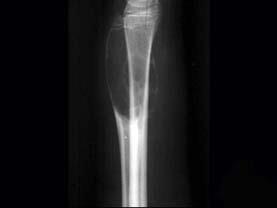

男性,17岁,近2年来感右前臂疼痛,肿胀,2周前由于疼痛加剧,查体右前臂压痛明显,皮肤稍显红肿,请结合所提供图像,选择最佳选项 ( )A、软骨...